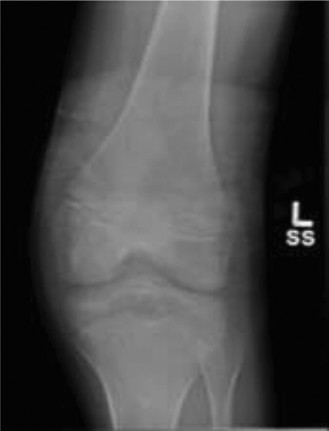

A 14-year-old male presents to your office with a chief complaint of swelling about the left knee and decreas…